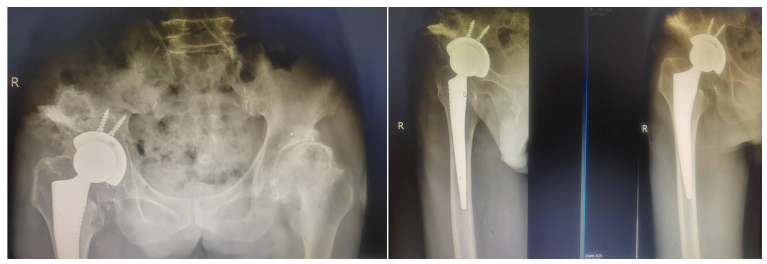

梁某某因双髋部疼痛10余年,反反复复,期间在当地医院进行过保守治疗,但是都没有取得很好的效果,尤其是近半年,患者右侧髋部疼痛症状加重,右下肢短缩、髋部活动受限,行走困难,严重影响日常活动。为了进一步治疗,在家人的陪同下慕名来到我院骨二科进行治疗。办理住院后,患者完善相关检查后,确诊为双侧髋关节发育不良,右侧严重。此症状保守治疗效果不佳,行全髋关节置换手术治疗是目前最有效的方法。但患者因长期的髋关节发育不良,导致髋关节周围肌肉韧带张力失衡、挛缩,髋关节解剖中心移位伴随脱位,髋臼侧畸形及骨量缺失等情况,手术难度较大,手术出现除普通髋关节置换的感染、血栓风险外,更容易出现假体脱位、假体周围骨折、神经血管损伤等并发症,这些都是需要考虑的问题。骨二科主任谢宝林组织科内医护人员对病例进行讨论,制定了详细的手术治疗方案、术后康复方案等,建议患者行手术治疗。告知患者及家属手术相关风险,他们表示理解,予行右侧全髋关节置换术,手术非常顺利,病情稳定。

在骨二科医护人员的共同努力下,梁某某术后第3天可拄助行器下床行走。通过术后康复治疗,梁某某行走良好,终于摆脱了困扰了他10年的关节疼痛症状。患者家属为表达感激之情,给骨二科全体医护人员送来锦旗!